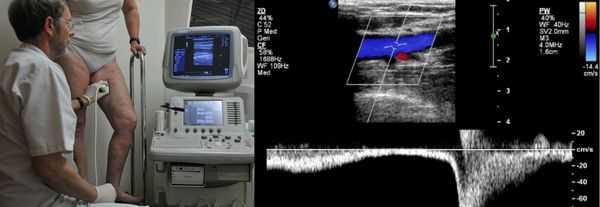

Проведение диагностики ХВН на ранних стадиях способствует ускорению лечения. При диагностике важно определить стадию заболевания. После общего клинического осмотра врач проводит дуплексное ангиосканирование вен нижних конечностей, чтобы определить тактику лечения. Дуплексное ангиосканирование поможет оценить состояние исследуемых сосудов, увидеть места их сужений или расширений, а также выявить тромбообразования.

Одним из самых доступных методов диагностики данного заболевания является УЗИ, главным преимуществом которого является многоразовость применения без рисков для здоровья, безболезненность, а также возможность выявить нарушения в текущей работе венозного аппарата. [3]

Для получения лучшего результата обследование рекомендуется проводить во второй половине дня. Поскольку именно после дневной нагрузки на ноги можно провести более точную оценку состояния клапанов, диаметра вен и степени поражённости стенок. На тактику лечения влияет наличие тромба в просвете вен, который приводит к нарушению тока крови и несёт наибольшую угрозу для жизни пациента.

Золотым стандартом считается дуплексное ангиосканирование. Этот метод сочетает в себе ультразвуковое исследование и доплеровское сканирование. Таким образом, можно в режиме реального времени увидеть состояние сосудистой стенки и оценить скорость кровотока в венозной системе нижних конечностей.